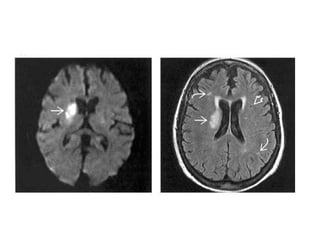

Diffusion Weighted Imaging (DWI)

• DWI is the most sensitive sequence for

stroke imaging.

DWI is sensitive to restriction of Brownian

motion of extracellular water due to

imbalance caused by cytotoxic edema.

Normally water protons have the ability to

diffuse extracellularly and loose signal.

High intensity on DWI indicates restriction

of the ability of water protons to diffuse

extracellularly.

This is why DWI is called 'the stroke

sequence'

• DWI is already positive in the acute phase

and then becomes more bright with a

maximum at 7 days.

• DWI in brain infarction will be positive for

approximately for 3 weeks after onset (in

spinal cord infarction DWI is only positive

for one week!).

MR Findings

• Tl WI: Small, well circumscribed hypointense foci

• T2WI: Small, well circumscribed hyperintense foci

• FLAIR:Typically increased in signal

• DWI

o Restricted diffusion (hyperintense) if acute/subacute

o May show small lesions otherwise undetectable

• Tl C+: May enhance if late acute/early subacute

• MRA: Normal